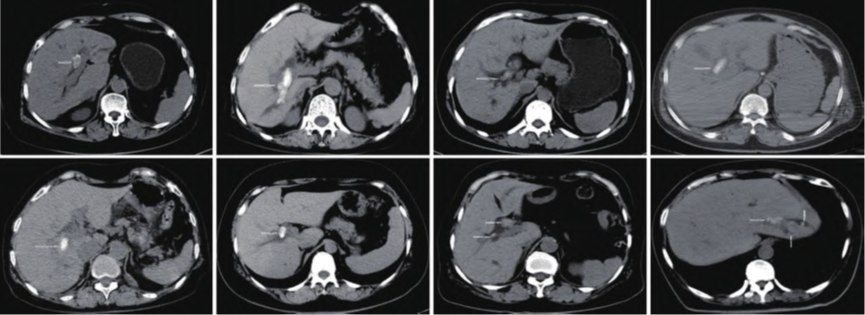

8Àý¸Îµ¨¹Ü½áʯ»¼ÕßÒºµçËéʯÖÎÁƵÄCTÌåÏÖ£¨°×É«¼ýÍ·ËùָΪ½áʯ£©